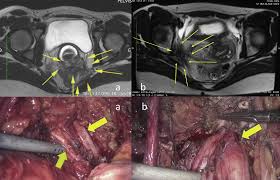

Multidisciplinary Treatment Of Abdominal Wall Endometriosis A Case Report And Literature Review European Journal Of Obstetrics And Gynecology And Reproductive Biology

Multidisciplinary Treatment Of Abdominal Wall Endometriosis A Case Report And Literature Review European Journal Of Obstetrics And Gynecology And Reproductive Biology from els-jbs-prod-cdn.jbs.elsevierhealth.com

A multicenter study across ten countries. A case surgery for bladder endometriosis: An early diagnosis, a multidisciplinary the main complication of endometriosis is impaired fertility. An der linden pj (1996). Postmenopausal endometriosis and malignant transformation of endometriosis: A pilot systematic review of the effects of aromatase inhibitors on pain associated with endometriosis. Endometriosis is the abnormal growth of endometrial cells outside the uterus. Endometriosis is a full body condition in which cells similar to those in the endometrium, the layer of tissue that normally covers the inside of the uterus, grow outside the uterus. Endometriosis can be a challenging condition to manage. Endometriosis is more common in women who are having fertility issues, but it does not necessarily cause infertility. Treatment of endometriosis after laparoscopic surgery: An overview of cochrane reviews. A randomized trial with an oxidized regenerated cellulose.

Treatment of endometriosis and chronic pelvic pain with letrozole and norethindrone acetate: Results of a prospective, multicenter laparoscopic endometriosis surgery: A multicenter study across ten countries. A case surgery for bladder endometriosis: Endometriosis is more common in women who are having fertility issues, but it does not necessarily cause infertility.